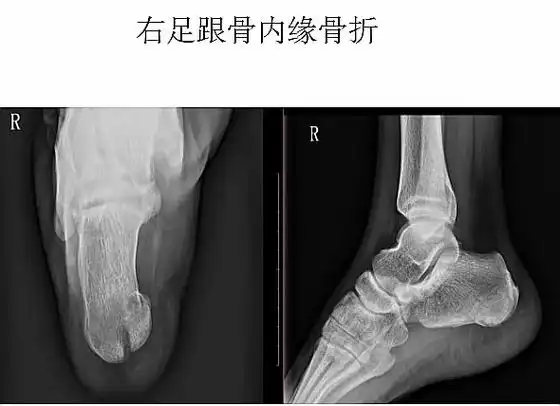

跟骨轴位常规拍摄方法:病人仰卧或坐于摄影台或者板凳上,对侧膝部弯曲